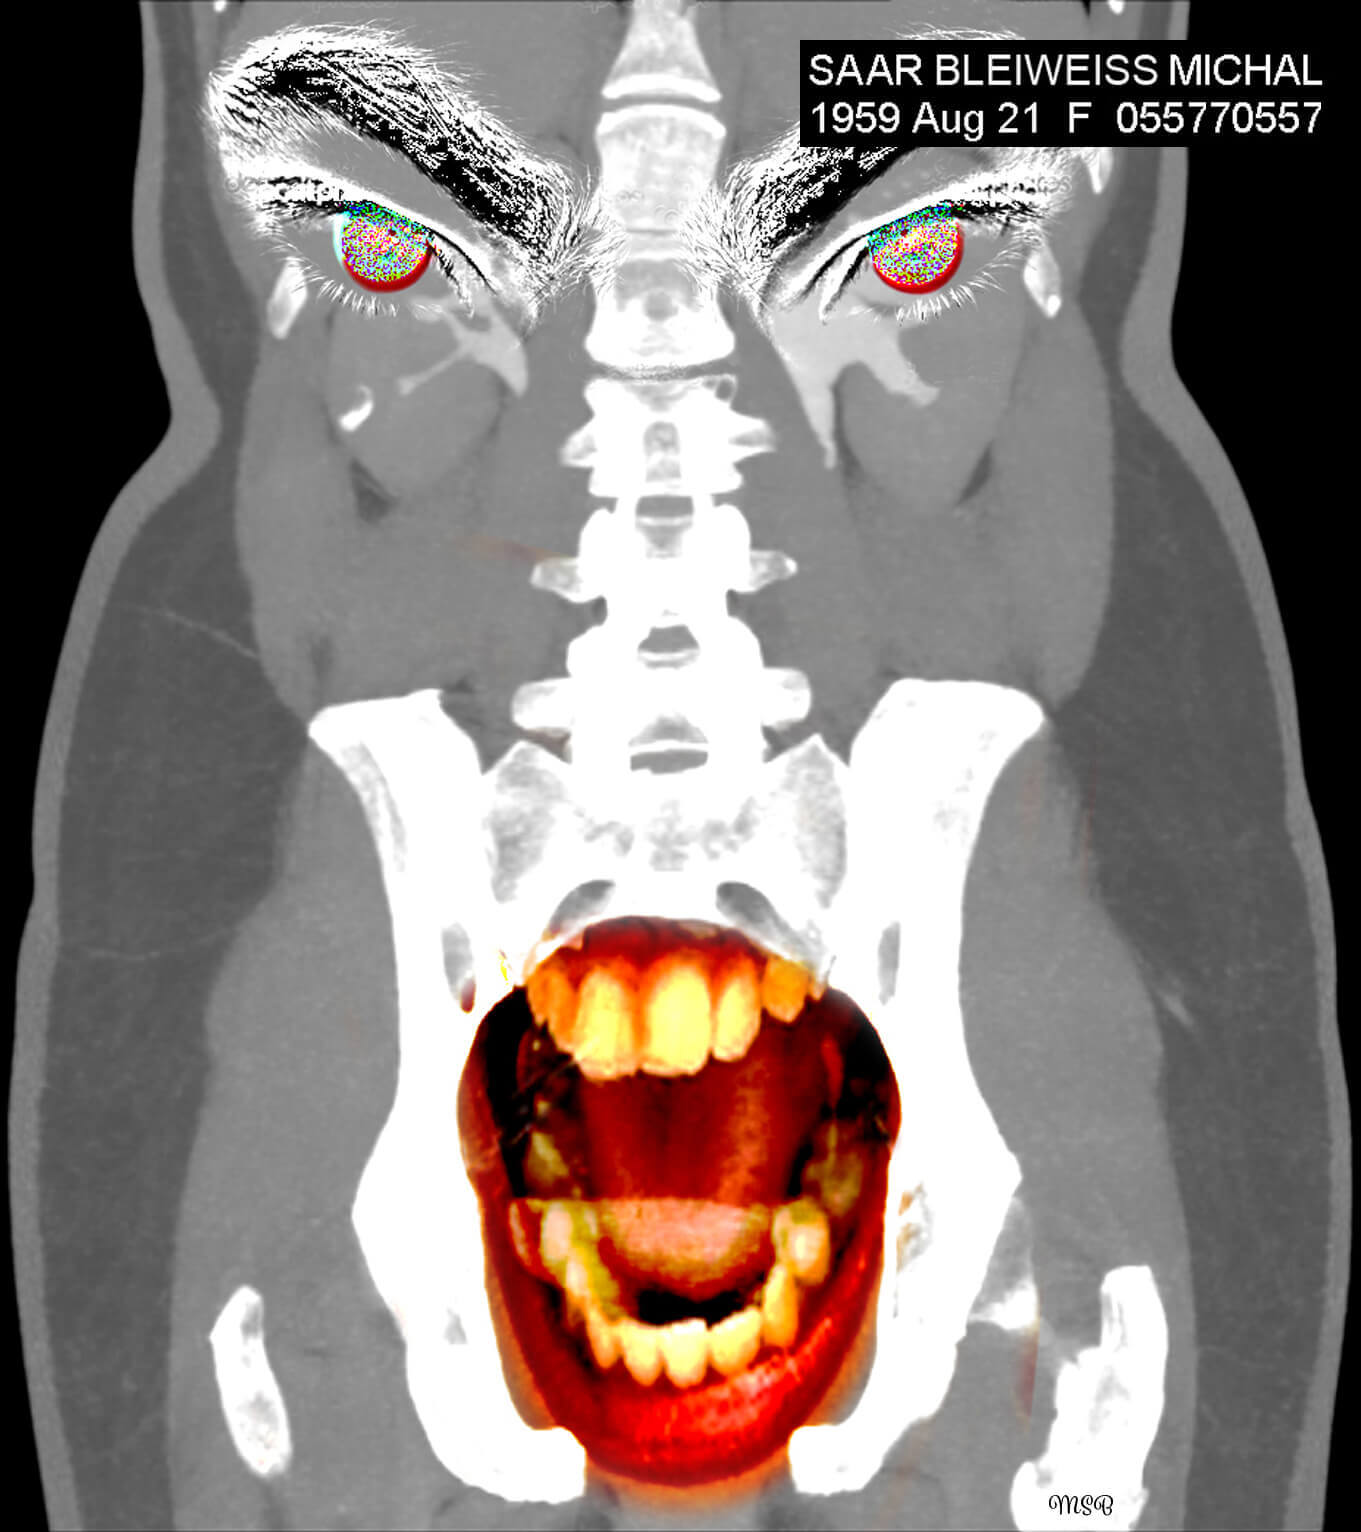

A reimagining of “self,” by Michal Saar-Bleiweiss

A few years ago, I became ill with Nephrostomy and had to undergo surgery. I was sitting with my husband, Mark, at a clinic in Ramat Aviv, Israel, in the office of a professor who specializes in CT* decoding. There, on two huge screens, for the first time I saw my body from the inside, and it was at this moment that my creative impulse arose.

The images before me were entirely in black and white, devoid of personality or character. There was no sign of the Michal that was me, and I felt a great desire and need to take these images to reinstate Michal, the person. When we returned home, I was curious about how I would feel when I looked at the images again—but this time on my computer screen. What I saw created an emotional storm within me.

This storm opened my “third eye,” enabling me to look inside myself. In my imagination I saw colors, dimensions, and expressive features, such as eyes. This was probably my way of internalizing my new reality, digesting what is going on inside me and brushing off my fears and pain. I wanted and needed to wake up each morning with a new smile and the ability to cope.

One of the few people I did share it with was a medical professor, who is also an artist in his own right. He introduced me to Harmony software, a simple drawing software program that enables the user to scribble and draw (primarily in black and white) with several types of brushes.

Having released the pain from the CT images, I found myself opening the next chapter in my imagination—creating digital collages.